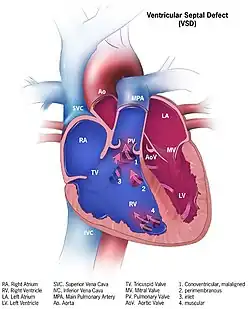

![]() | |

| Illustration showing various forms of ventricular septal defects. 1. Conoventricular, malaligned 2. Perimembranous 3. Inlet 4. Muscular | |

Although there are several classifications for VSD, the most accepted and unified classification is that of Congenital Heart Surgery Nomenclature and Database Project.[14] The classification is based on the location of the VSD on the right ventricular surface of the inter ventricular septum and is as follows:

Multiple

Type 1

Type 1 is sub aortic

Type 2

- Type 2 also known as perimembranous, paramembranous, conoventricular, membranous septal defect, and subaortic.

- Most common variety found in 70%

Type 3

Type 3 also known as inlet (or AV canal type).

- Commonly associated with atrioventricular septal defect, found in about 5%

Type 4

Type 4 also known as muscular (trabecular)

- Located in the muscular septum, found in 20%. Can be sub classified again based on the location into anterior, apical, posterior and mid

Type: Gerbode

Type: Gerbode also known as left ventricular to right atrial communication

- Due to absence of Atrioventricular septum.